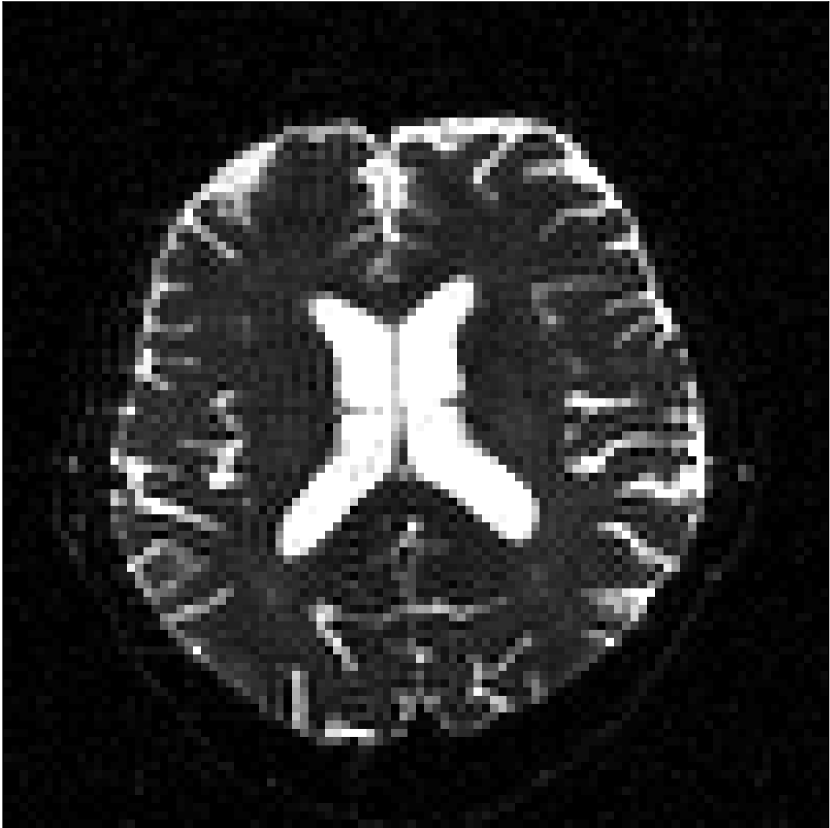

Figure 8 shows examples of non-diffusion-weighted images before and after processing. The raw images (Raw) served as the input for the magnitude deep learning (MCNN) and complex deep learning (CCNN) methods.

Raw 𝐱tsubscript𝐱𝑡\mathbf{x}_{t}

MCNN, fθ^(𝐱t)subscript𝑓^𝜃subscript𝐱𝑡f_{\hat{\theta}}\left(\mathbf{x}_{t}\right)

MCNN Resid., Ric(𝐱t)fθ^(𝐱t)Ricsubscript𝐱𝑡subscript𝑓^𝜃subscript𝐱𝑡\text{Ric}(\mathbf{x}_{t})-f_{\hat{\theta}}\left(\mathbf{x}_{t}\right)

CCNN, fθ^(𝐱t)subscript𝑓^𝜃subscript𝐱𝑡f_{\hat{\theta}}\left(\mathbf{x}_{t}\right)

CCNN Resid., Ric(𝐱t)fθ^(𝐱t)Ricsubscript𝐱𝑡subscript𝑓^𝜃subscript𝐱𝑡\text{Ric}(\mathbf{x}_{t})-f_{\hat{\theta}}\left(\mathbf{x}_{t}\right)

No PF

5/8 PF

Figure 8: Examples of non-diffusion-weighted images from in vivo data at b=0𝑏0b=0 s/mm2. Artifacts in the Raw image, 𝐱tsubscript𝐱𝑡\mathbf{x}_{t}, are corrected by the MCNN and CCNN models, fθ^(𝐱t)subscript𝑓^𝜃subscript𝐱𝑡f_{\hat{\theta}}(\mathbf{x}_{t}). Also shown are the residuals between the CNN corrections and the original Raw image with Rician bias correction Ric(𝐱t)Ricsubscript𝐱𝑡\text{Ric}(\mathbf{x}_{t}) [10]. The Gibbs artifacts removed by the methods are observed in the residuals. The MCNN method introduces some banding artifacts at the PF 5/8ths factor that are not present in the CCNN method.

Both methods remove artifacts, but the MCNN method allows residual rippling artifacts to pass through in the presence of partial Fourier. These rippling artifacts are not present in the CCNN method.